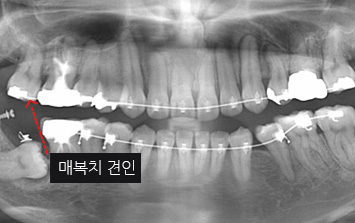

26세 여환으로 우측 아래 어금니 매복으로 다른 치과에서는 어금니 2개를 모두 발치 해야 한다는 진단을 받고 내원.

환자분이 매복된 치아를 꼭 살리고 싶다고 하여 사랑니는 발치를 하고 매복되어 있는 치아는 교정으로 견인 하기로 함.

구강외과 협진으로 안정적으로 사랑니를 발치하고 치아교정을 진행하였습니다.

어금니와 사랑니가 수평 매복되어 있는 상황

사랑니 발치 후 매복된 치아 견인

교정 후 치조골 또한 온전하게 재생됨

구강외과 협진- 사랑니를 발치 한 이유는 매복치아를 발치 할 경우 다량의 뼈를 제거해야 하고

그로 인하여 아래턱뼈가 약해질 가능성이 있다고 판단했기 때문입니다.